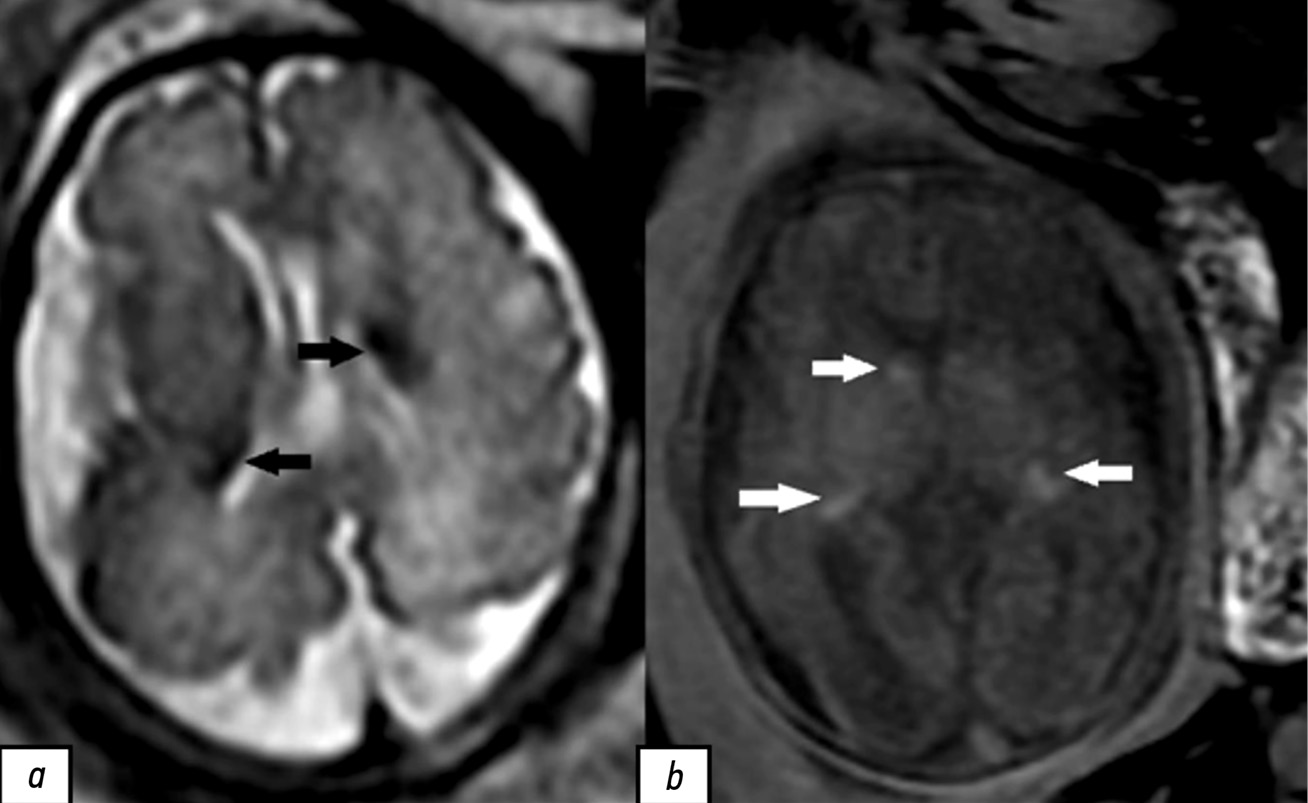

При проведении УЗИ беременной 26 лет на сроке 28 нед. и 2 дня обнаружено наличие объёмных образований в сердце у плода. Выявленные образования не имели кровотока по данным цветового допплеровского картирования и лоцировались в левом желудочке, толще межжелудочковой перегородки и полости правого предсердия (рис. 1). Учитывая наличие сомнительных результатов УЗИ, консилиум в составе врачей-генетиков и врачей-акушеров-гинекологов принял решение провести пренатальную МРТ плода.

Рис. 1. Результаты пренатального ультразвукового исследования сердца плода в III триместре беременности (срок 28 нед. и 2 дня). Визуализируются вытянутой формы гиперэхогенные образования: a — в толще межжелудочковой перегородки; b — в полости левого желудочка.

По данным пренатального УЗИ плода на сроке 39 нед. и 5 дней по-прежнему визуализировались образования: в левом желудочке сердца с размером 16,0×9,1 мм, в толще межжелудочковой перегородки — 11,7×5,9 мм, в полости правого предсердия — 16,8×13,1 мм. При проведении цветового допплеровского картирования кровоток в образованиях не обнаружен, что подтверждает ранние данные о возможной рабдомиоме сердца у плода.